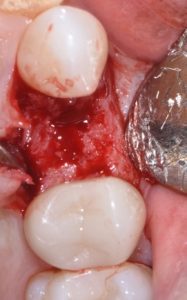

This video demonstrates alveolar ridge preservation following atraumatic surgical extraction of an endodontically treated tooth. Emphasis is placed on minimizing surgical trauma to preserve existing hard and soft tissues.

The case features flap management in the presence of a buccal dehiscence, followed by bone graft placement and stabilization using a dense polytetrafluoroethylene (d-PTFE) membrane. Surgical principles, membrane selection, and handling techniques are discussed to optimize ridge dimensions and facilitate future implant placement.